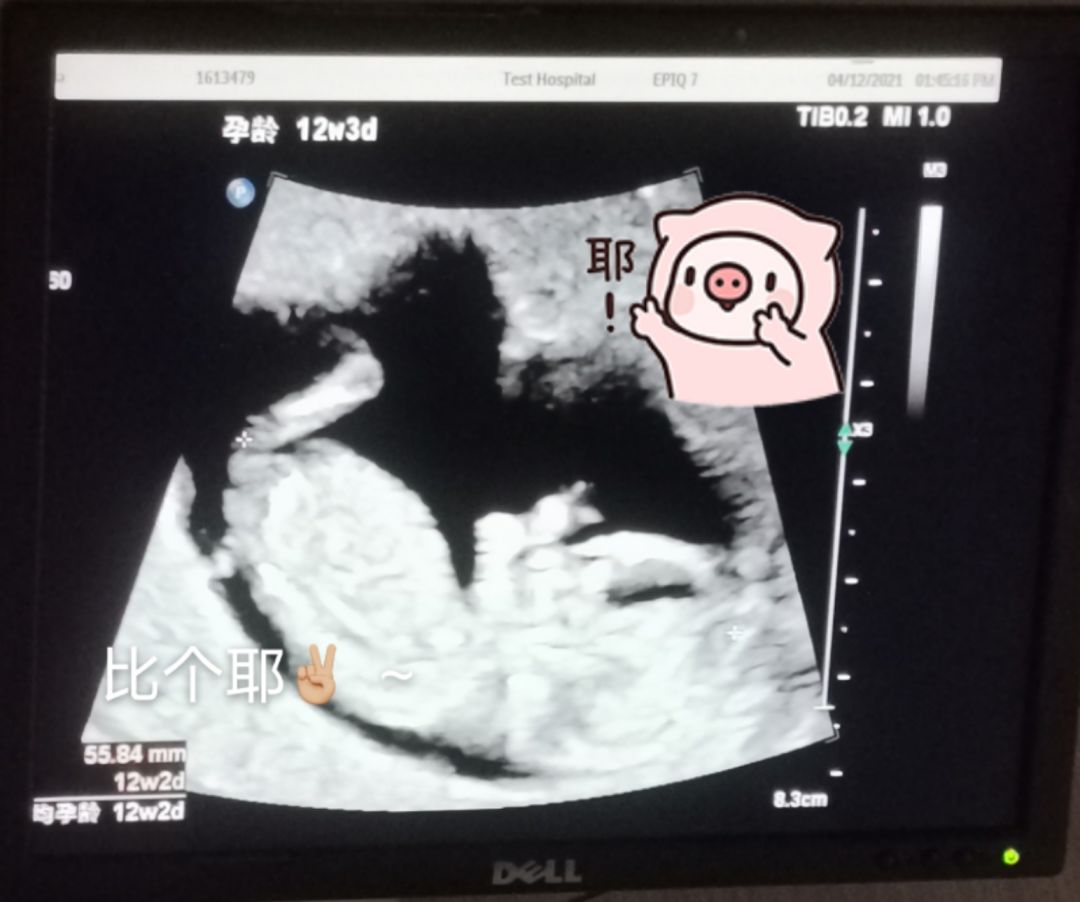

来来,给你介绍一下余二宝,

TA在比耶呢,太神奇了~